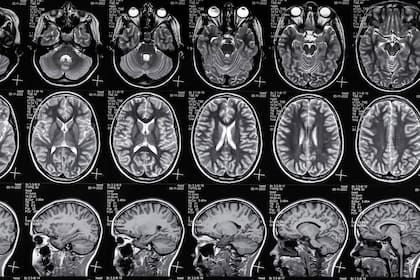

Investigadores de la Universidad de Buenos Aires (UBA) están utilizando redes neuronales artificiales para que una Inteligencia Artificial (IA) aprenda a identificar el inicio del Alzheimer en imágenes de resonancias magnéticas. A la vez, ver estas redes neuronales artificiales en acción permite una libertad sin igual para conocer cómo es que funciona el cerebro humano.

Quien explica el trabajo que se lleva adelante en la UBA es Diego Fernández Slezak, investigador del Instituto de Ciencias de la Computación UBA/CONICET y profesor en la Facultad de Ciencias Exactas y Naturales de la UBA: “Nosotros usamos la IA para codificar el cerebro. Cuando se le hace una resonancia magnética al cerebro de una persona, lo que vemos son píxeles o vóxeles de colores, que son pedacitos del cerebro que se iluminan o no se iluminan en función de lo que está pasando en esa zona del cerebro. Si lo que se ilumina es normal o no, es difícil de identificar incluso para los especialistas. Entonces, la IA toma las imágenes, las codifica, y devuelve índices que podrían permitir asociarlos a patologías, como por ejemplo Alzheimer, bipolaridad, ACV o epilepsia”.

El trabajo que está haciendo Fernández Slezak y colegas es el de reconocer un patrón en las imágenes de resonancias magnéticas del cerebro que le permita a una computadora con inteligencia artificial identificar el Alzheimer de forma temprana.

“Ahora estamos trabajando con imágenes y cómo codificar, con resonancias magnéticas del cerebro, atributos que lleven al Alzheimer”, sumó el experto en un texto difundido por la universidad porteña y sumó: “Esta es una enfermedad muy bien caracterizada, y que está en constante estudio. Actualmente, existen muy buenos tratamientos para retrasar los efectos que afectan la calidad de vida, así es que detectarlo a tiempo es algo vital”.

Se trata de una investigación en curso en colaboración con la Fundación para la Lucha contra las Enfermedades Neurológicas de la Infancia (Fleni), que es quien aporta las resonancias magnéticas con las que se le está enseñando a la IA. Para que pueda conocer todo el camino que lleva a una enfermedad como el Alzheimer, se inicia con lo que se conoce como queja subjetiva de un paciente. Es decir, alguien que tiene olvidos, o se confunde los nombres.

Los especialistas entonces le realizan al paciente una batería de estudios, entre los que se encuentra la resonancia magnética, para saber si esa queja subjetiva efectivamente se corresponde con un problema cerebral real. Esto podría ser el inicio de una demencia que podría luego degenerar en Alzheimer, o tal vez una afasia, u otra patología cerebral.

“El Fleni tiene una base de datos de miles de resonancias viejas”, contó el experto y agregó: “Nosotros lo que hacemos primero es que la IA codifique la estructura del cerebro, y después lo que tenemos que hacer es asociar esa estructura a las distintas patologías. Se ve en el historial de diagnóstico, y se ve si una dirección dada de la estructura del cerebro, es la dirección del Alzheimer, o de cada una de las otras patologías”.